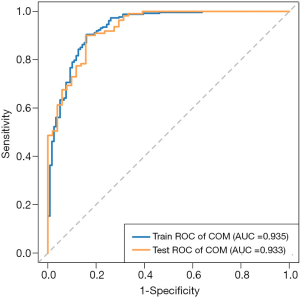

AI model prediction results

The above eight feature parameters were trained and tested for classification using LASSO to understand their ability to discriminate between COM and non-COM stones. The sensitivity, specificity and accuracy of the AI model were 90.5%, 84.3% and 88.5% for the training set, and 90.1%, 84.3% and 88.3% for the testing set. The AUC of the training set was 0.935 [95% confidence interval (CI): 0.907–0.962], the AUC of the testing set was 0.933 (95% CI: 0.893–0.973), and the optimal cut-off value based on the training set was 0.470 (Figure 5).

In this study, the most commonly used unenhanced urinary tract CT and AI technology were combined to construct a COM stone prediction model using the LASSO algorithm. The accuracy of COM prediction was 88.3%, and the sensitivity and specificity of AI model were 90.1% and 84.3%, respectively. The AUC of the testing set reached 0.933, suggesting that the model could accurately distinguish COM from non-COM stones, which was basically consistent with the performance of the previously reported DECT model (16,30).